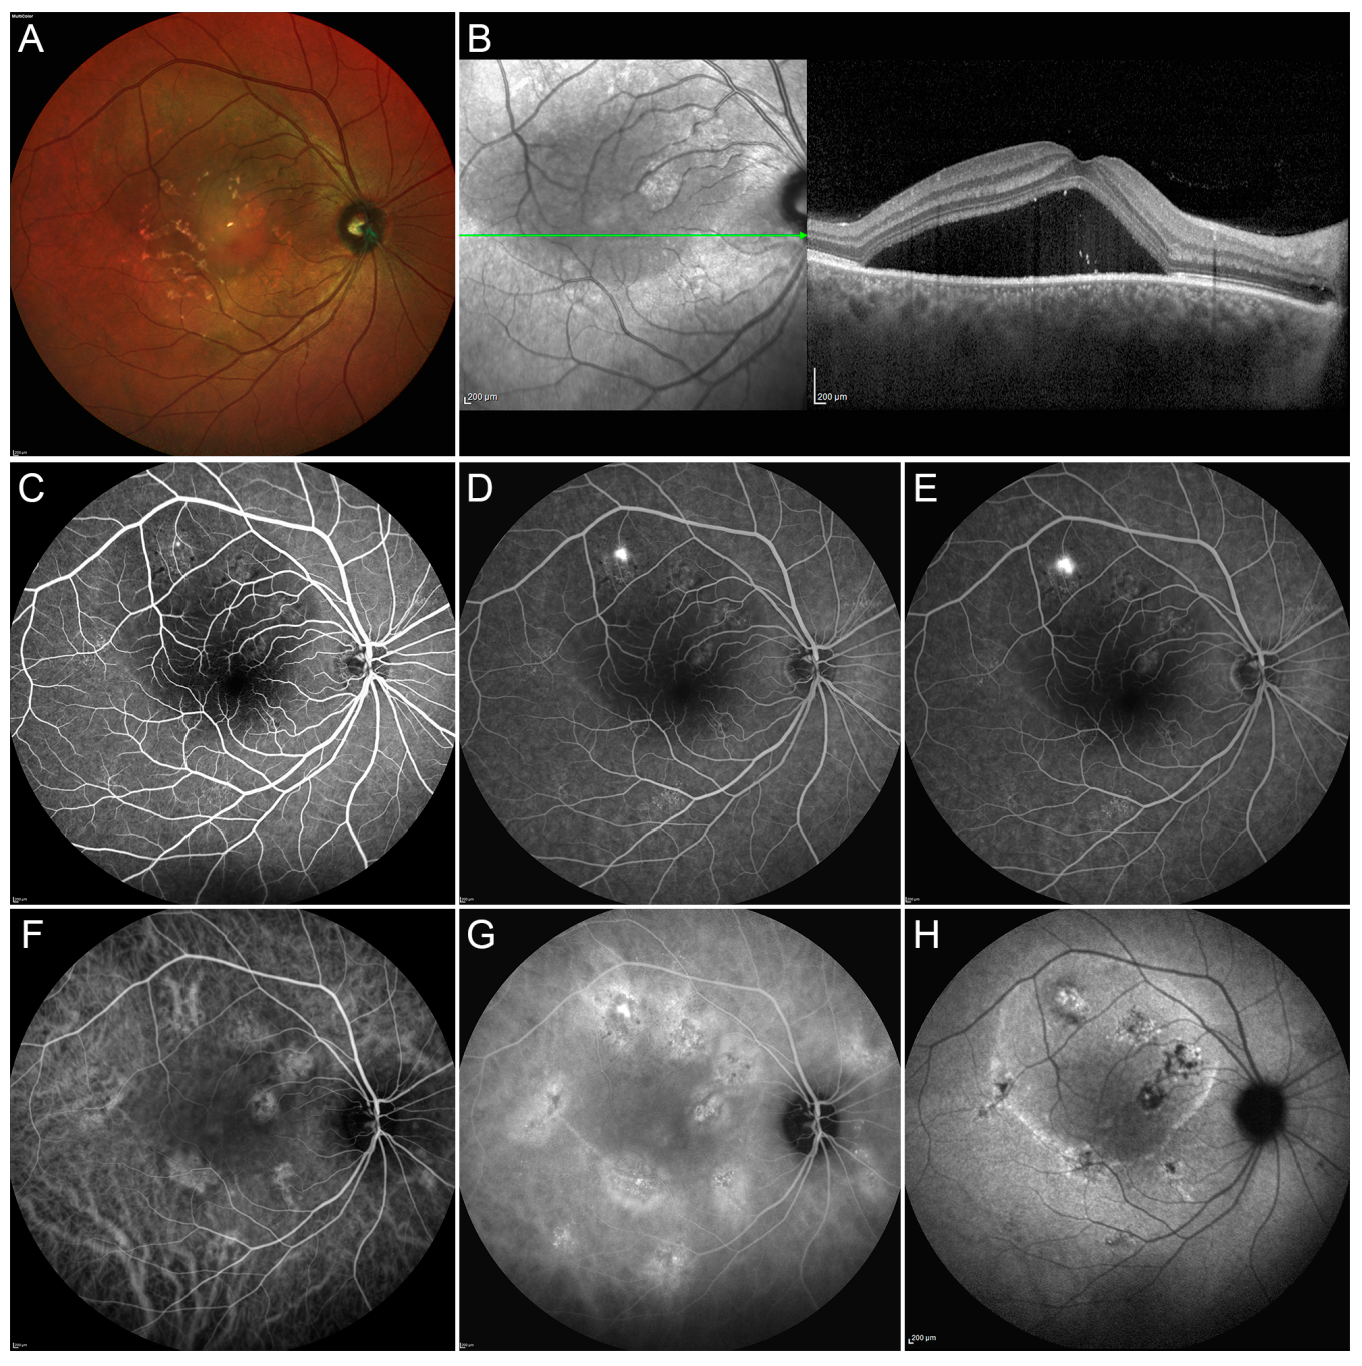

Figure 1.

Multimodal Imaging in a case of acute central serous chorioretinopathy (CSC). Multicolor image (A) shows the presence of a massive subretinal fluid accumulation involving a big part of the posterior pole. Structural optical coherence tomography OCT scan (green arrow) (B) confirms the presence of a large subretinal exudation associated with a pachychoroid. Fluorescein angiography (FA) discloses a region of hypofluorescence, secondary to the masking effect caused by the subretinal fluid, with a well-defined leaking point and no other detectable alterations in the early, intermediate and late phases (C–E, respectively). The early phase of indocyanine green angiography ICGA (F) discloses the presence of multiple alterations of the choroidal vascular network, better highlighted in the intermediate phase of the examination (G). Fundus autofluorescence demonstrates the hyperfluorescence corresponding to the active leaking point and the combination of hypo/hyper-fundus autofluorescence in the site of retinal pigment epithelium decompensation (H). This case was simply monitored until complete spontaneous resolution of the neurosensory detachment.